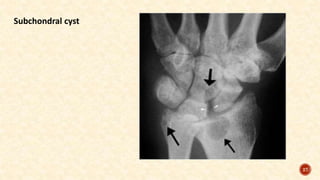

X-rays of both hands and of the affected joints:

Reduced joint space

Erosion of articular margins

Subchondral cysts

Juxta-articular rarefaction

Soft tissue shadow at the level of the joint because of joint effusion or synovial

hypertrophy

Deformities of the hand and fingers

Subchondral cyst